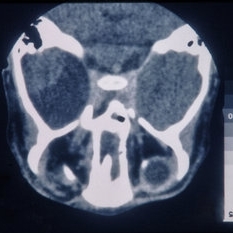

CT Scan of Brain Showing Cerebral Hypoplasia

CT Scan of Brain Showing Cerebral Hypoplasia

Feb 20 2015 by H. Michael Lambert, MD

CT scan of brain showing cerebral hypoplasia

Condition/keywords: cerebral hypoplasia, CT scan, linear nevus sebaceous syndrome